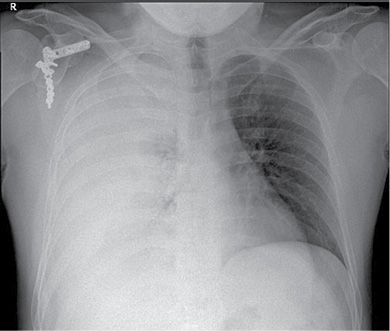

36 m. vyras P. D. atvyko į Gastroenterologijos skyrių patikslinti diagnozės planine kepenų biopsija. Praėjus 8 val. po procedūros, pacientas pajuto maudimą po dešiniuoju šonkaulių lanku punkcijos vietoje. Apžiūros metu pacientas buvo hemodinamiškai stabilus. Atlikus laboratorinius tyrimus, nustatyta saiki anemizacija (hemoglobinas – 128 g/l; norma – 135–160 g/l). Įtariant kraujavimą pilvaplėvėje, atlikta pilvo echoskopija: pilvo ertmėje laisvo skysčio nematyti, dešinėje pleuroje iki 4 cm laisvo skysčio ruožas. Konsultuota krūtinės chirurgo. Rekomenduota atlikti krūtinės ląstos rentgenogramą (Ro). Nustatytas beveik neoringas dešinysis plautis, pastebėta hidrotorakso požymių (1 pav.). Įtarus jatrogeninį hemotoraksą, krūtinės chirurgas atliko diagnostinę pleuros punkciją. Patvirtinus hemotorakso diagnozę, drenuota dešinė pleuros ertmė, išsiskyrė 400 ml kraujo. Tuo metu aktyvaus kraujavimo nenustatyta, hemodinamika išliko stabili, kartotiniuose laboratoriniuose tyrimuose – saiki anemizacija (hemoglobinas – 120 g/l). Atlikus kontrolinę rentgenogramą, nustatytas sumažėjęs skysčio kiekis pleuroje, buvo matyti kompresinių dešiniojo plaučio pakitimų. Įtariant sukrešėjusį hemotoraksą, atlikta skubi krūtinės ląstos KT (2 pav.), kuri patvirtino įtariamą patologiją. Tolesniam operaciniam gydymui pacientas perkeltas į Krūtinės chirurgijos skyrių. Atlikta skubi VATS (angl. video assisted thoracoscopic surgery). Operacijos metu pašalinta 1 000 ml krešulių, aktyvaus kraujavimo nenustatyta, diafragmos kupole rasta nedidelė hematoma. Pooperacinis periodas sklandus (3 pav.). Po trijų dienų geros būklės pacientas išleistas į namus.

1 pav. Krūtinės ląstos priekinė rentgenograma prieš operaciją